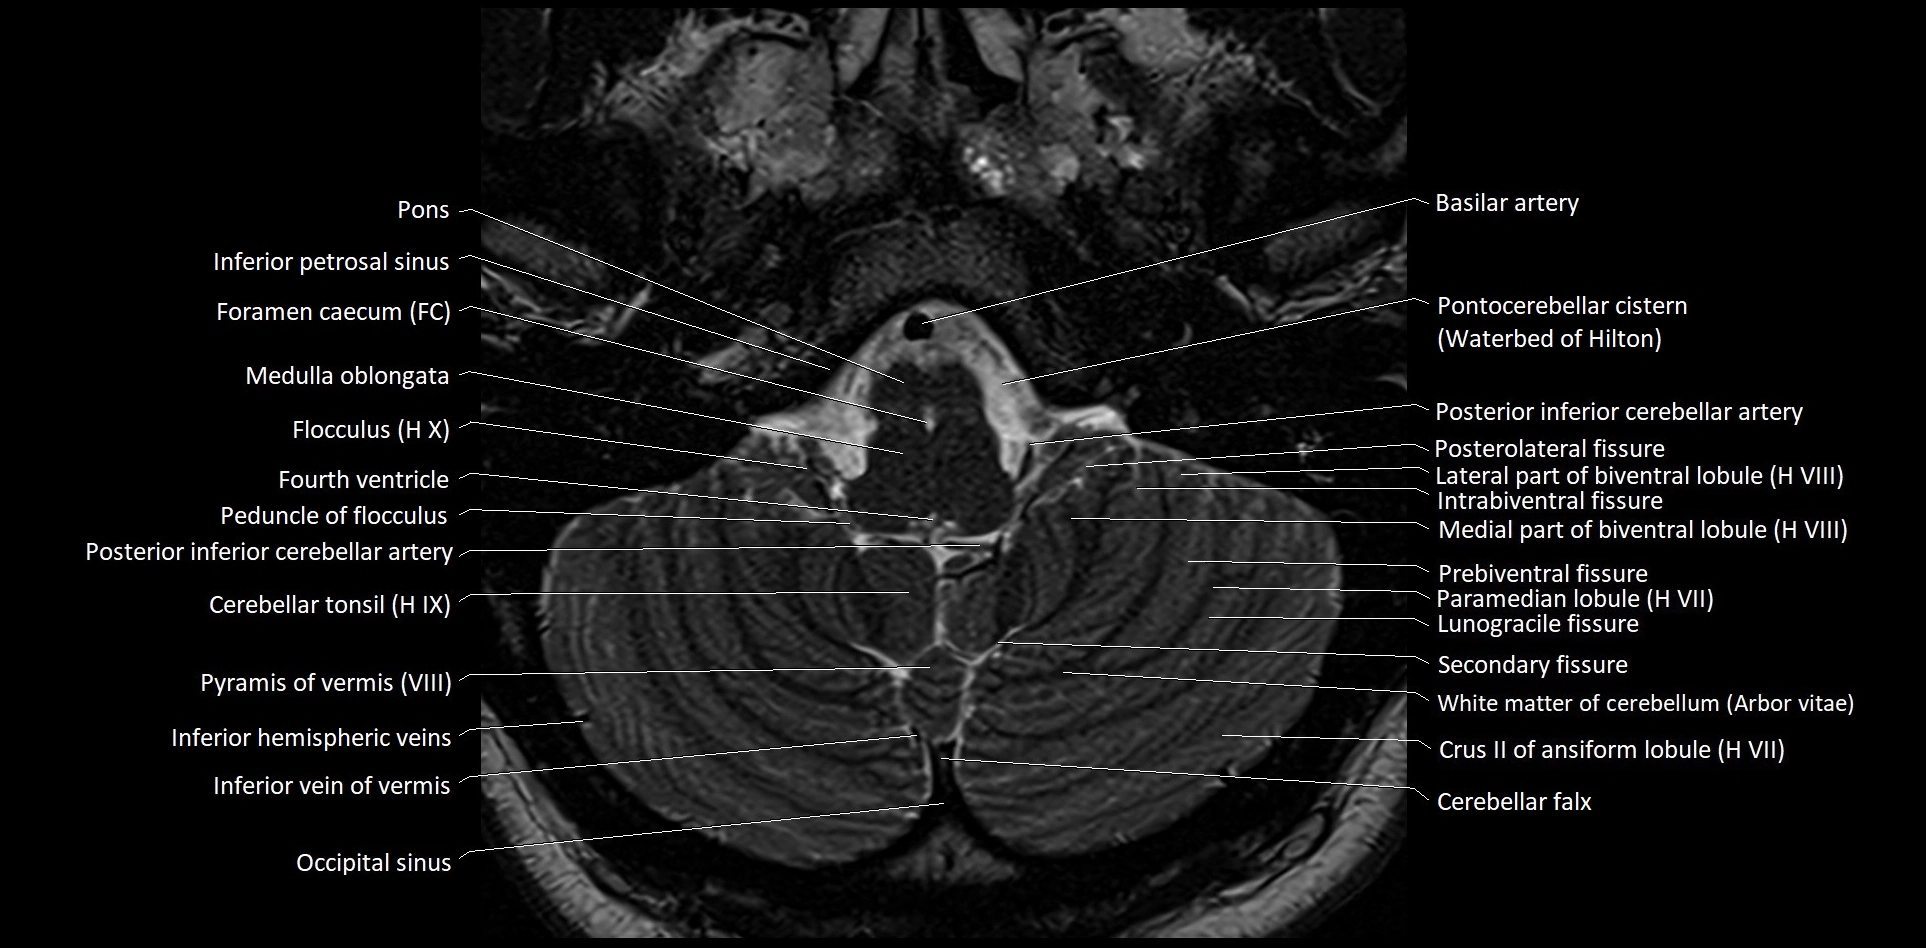

MRI images